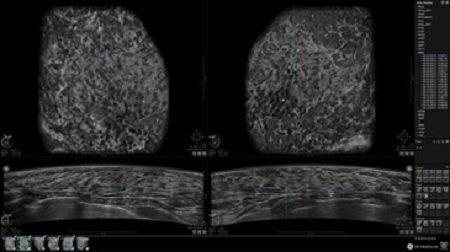

GE INVENIA ABUS – это современный УЗИ аппарат, который создан для точной и эффективной диагностики сканирования с высокой плотностью молочных желез. Выявляемость патологий раковых и предраковых стадий заболевания составляет 55%, что в конечном счете позволяет ставить врачу точные и своевременные диагнозы. Традиционные методы использования маммографии не показывают такой выявляемости, ограничиваясь лишь 3-38%.

УЗИ-аппарат GE INVENIA ABUS позволяет проводить максимально операторонезависимые процедуры, что значительно снижает риск неправильной постановки диагноза и сопутствующие издержки на обработку информации. Система готовит отчет в течение 3-х минут после сканирования, это безусловное преимущество по сравнению с обычным УЗИ сканером.

• датчик с изогнутой апертурой для качественного исследования

• сканирование одной грудной железы в трех проекциях не более 60 сек.;

• обработка результатов за три минуты.

• Отображение объемных 3D ультразвуковых изображений, которые состоят из традиционных поперечных и воссозданных коронарных и сагиттальных проекций

• Стандартизованная ориентация изображения: «толстый срез» в коронарной плоскости; поперечная; сагиттальная плоскость; радиальный и антирадиальный поворот изображения; просмотр исключительно области интереса

• Одновременный просмотр двух изображений для сопоставления в коронарной плоскости